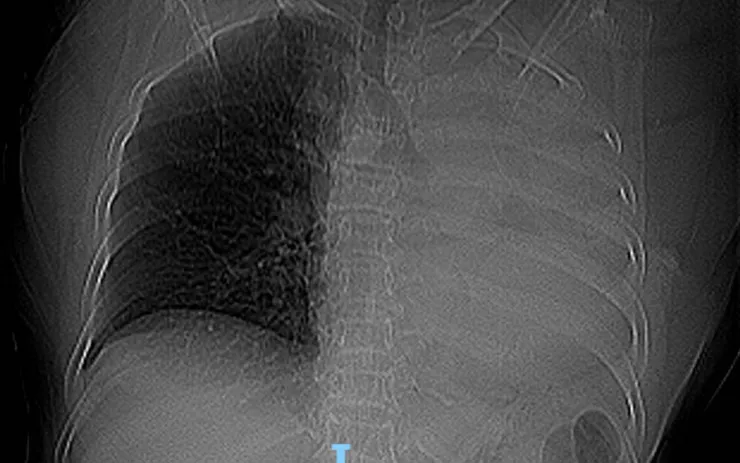

Khoa Cấp cứu - Bệnh viện Đa khoa khu vực Quảng Nam (Đà Nẵng) tiếp nhận một bệnh nhân nhập viện trong tình trạng ho nhiều đột ngột, kèm khó thở sau khi uống thuốc. Trên phim X-quang ngực, các bác sĩ ghi nhận hình ảnh mờ đậm toàn bộ trường phổi trái, nghi ngờ tổn thương nặng ở đường thở.

Ngay sau đó, người bệnh được chỉ định chụp CT ngực. Kết quả cho thấy xẹp hoàn toàn phổi trái do khối nằm trong lòng phế quản gốc trái, ban đầu đặt ra nghi vấn u phế quản hoặc dị vật đường thở. Với diễn tiến khởi phát đột ngột, các bác sĩ nghĩ nhiều đến khả năng dị vật và nhanh chóng hội chẩn chuyên môn.